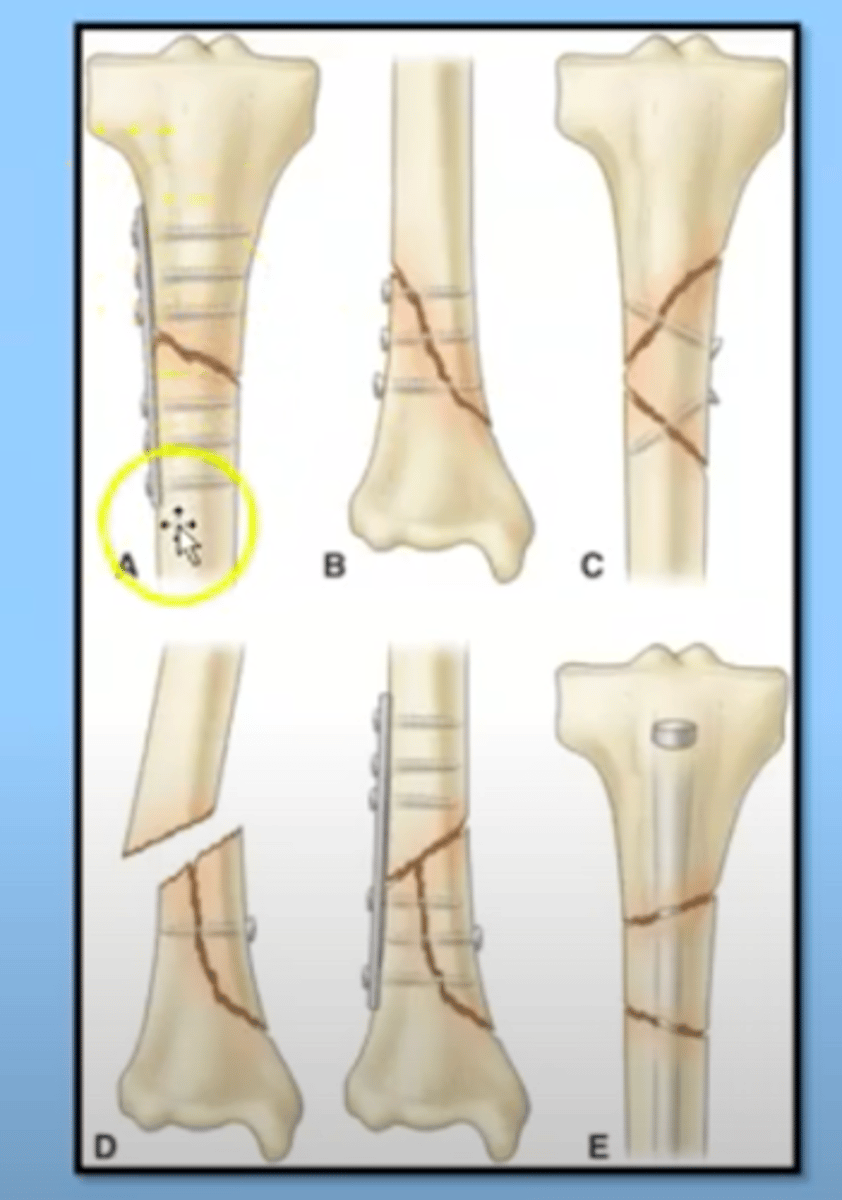

Medical management of fractures

Reduction

-closed

-open

Immobilization

-internal

-external fixation

-May require a surgical procedure to get the bone back in place and they have fixation (various devices, often screws or shafts that are put in place to maintain the bone in alignment so it can heal)

-some fixation devices are temporary, some permanent

internal immobilization

placed in surgery and the skin is closed over

external immobilization

the usage of devices that go right through the skin to immobilize